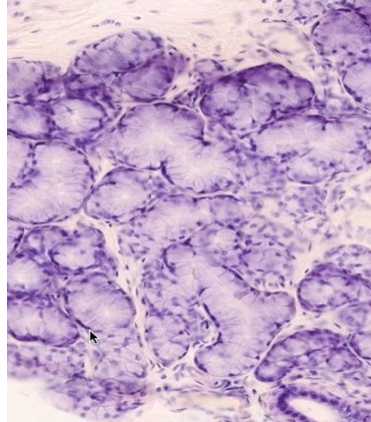

ID this cell type and name where you would find this type of tissue

Mucous cells

Sublingual gland (mixed but mostly mucous cells)

(Weakly staining, flat nuclei)